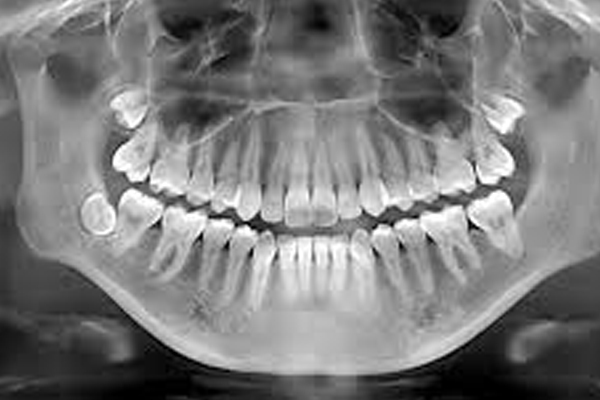

Dental X-rays provide a detailed view of teeth and bones, aiding diagnosis. They reveal hidden issues like decay, infections, or impacted teeth. X-rays are a crucial tool for planning precise dental treatments.